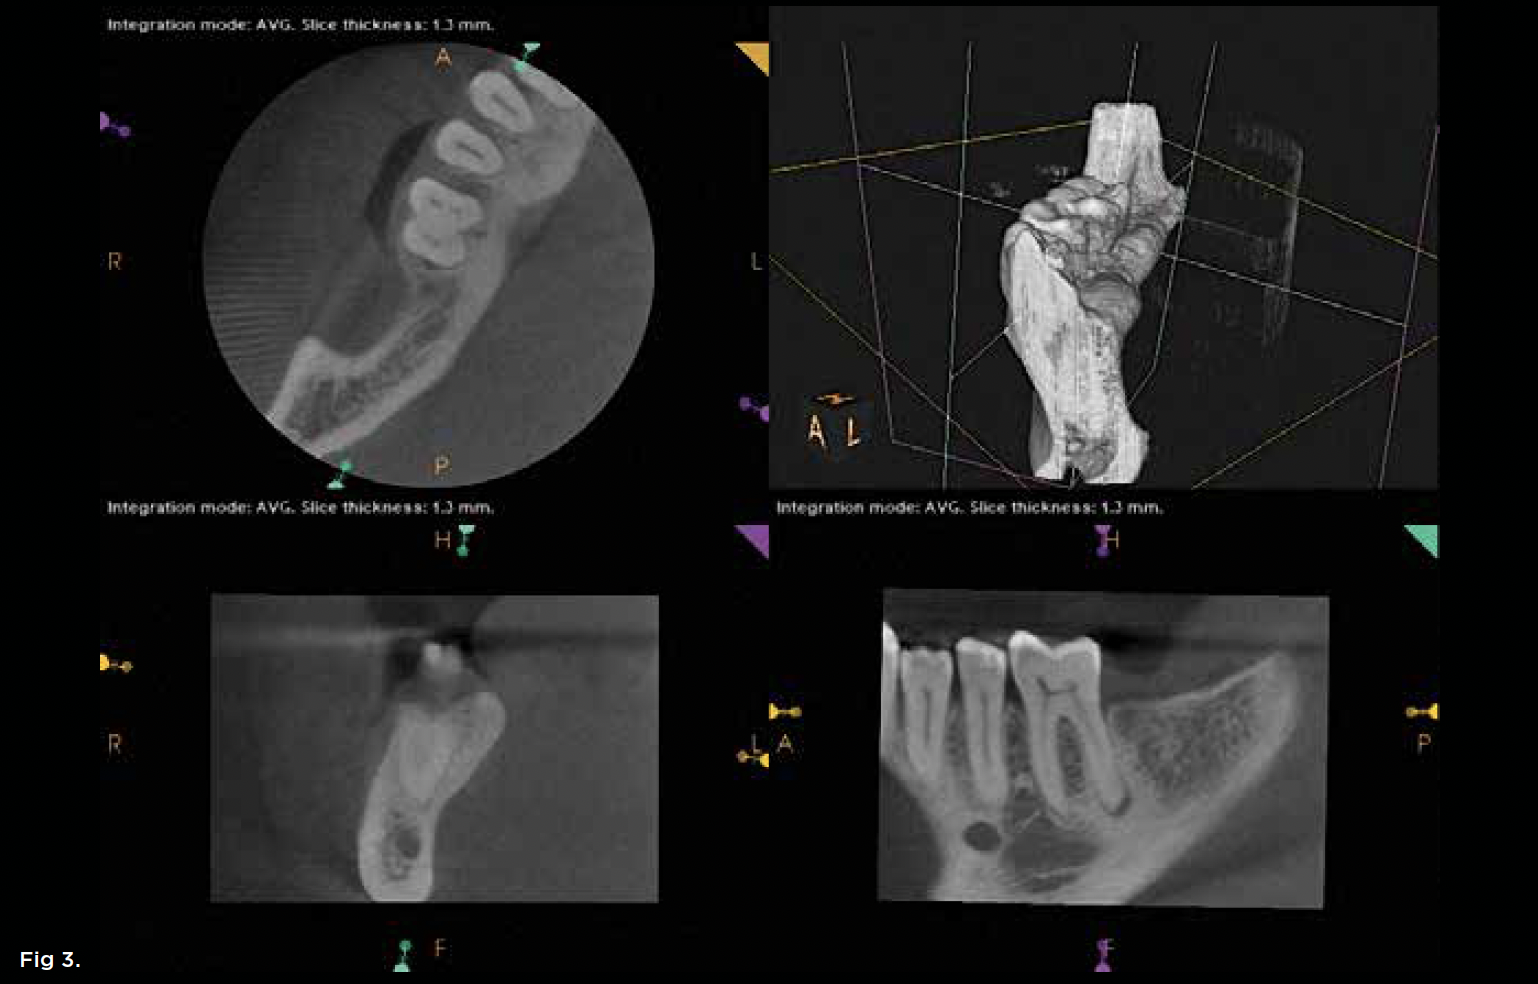

The extent of any crestal bone defects can impact recommendations. Teeth with extensive crestal bone defects whose further enlargement would complicate future implant replacement, for example, might be better suited to extraction. When discussing such issues with patients, the conversation should be detailed and accompanied by visual aids such as radiographs and/or illustrations, and include a thorough review of risks and benefits in both the short and long term. A case of fracture necrosis and periapical infection is presented in Figure 2 and Figure 3. Figure 1, to reiterate, summarizes the proposed treatment algorithm for unseparated fractures.

Fig 2. A 63-year-old male patient presented with a chief complaint of spontaneous pain and pressure discomfort of 3-week duration. A distal fracture line was visible on tooth No. 30, with a localized 7 mm deep periodontal probing depth adjacent to its distal aspect. The tooth had no response to pulp sensitivity testing and was sensitive to percussion. Periapical imaging (Fig 2) revealed a tooth with a shallow restoration and early signs of apical pathology. CBCT imaging (Fig 3, axial view, top left; and sagittal view, bottom right) confirmed early signs of apical pathology and showed localized crestal bone loss adjacent to the distal fracture line. A diagnosis of pulpal necrosis with symptomatic apical periodontitis was made, and the fracture was determined to involve root structure given the periodontal findings and radiographic crestal bone loss noted. The patient elected to pursue extraction with implant replacement given the reduced long-term prognosis for maintenance of the tooth.

Figure 2

Fig 3. A 63-year-old male patient presented with a chief complaint of spontaneous pain and pressure discomfort of 3-week duration. A distal fracture line was visible on tooth No. 30, with a localized 7 mm deep periodontal probing depth adjacent to its distal aspect. The tooth had no response to pulp sensitivity testing and was sensitive to percussion. Periapical imaging (Fig 2) revealed a tooth with a shallow restoration and early signs of apical pathology. CBCT imaging (Fig 3, axial view, top left; and sagittal view, bottom right) confirmed early signs of apical pathology and showed localized crestal bone loss adjacent to the distal fracture line. A diagnosis of pulpal necrosis with symptomatic apical periodontitis was made, and the fracture was determined to involve root structure given the periodontal findings and radiographic crestal bone loss noted. The patient elected to pursue extraction with implant replacement given the reduced long-term prognosis for maintenance of the tooth.